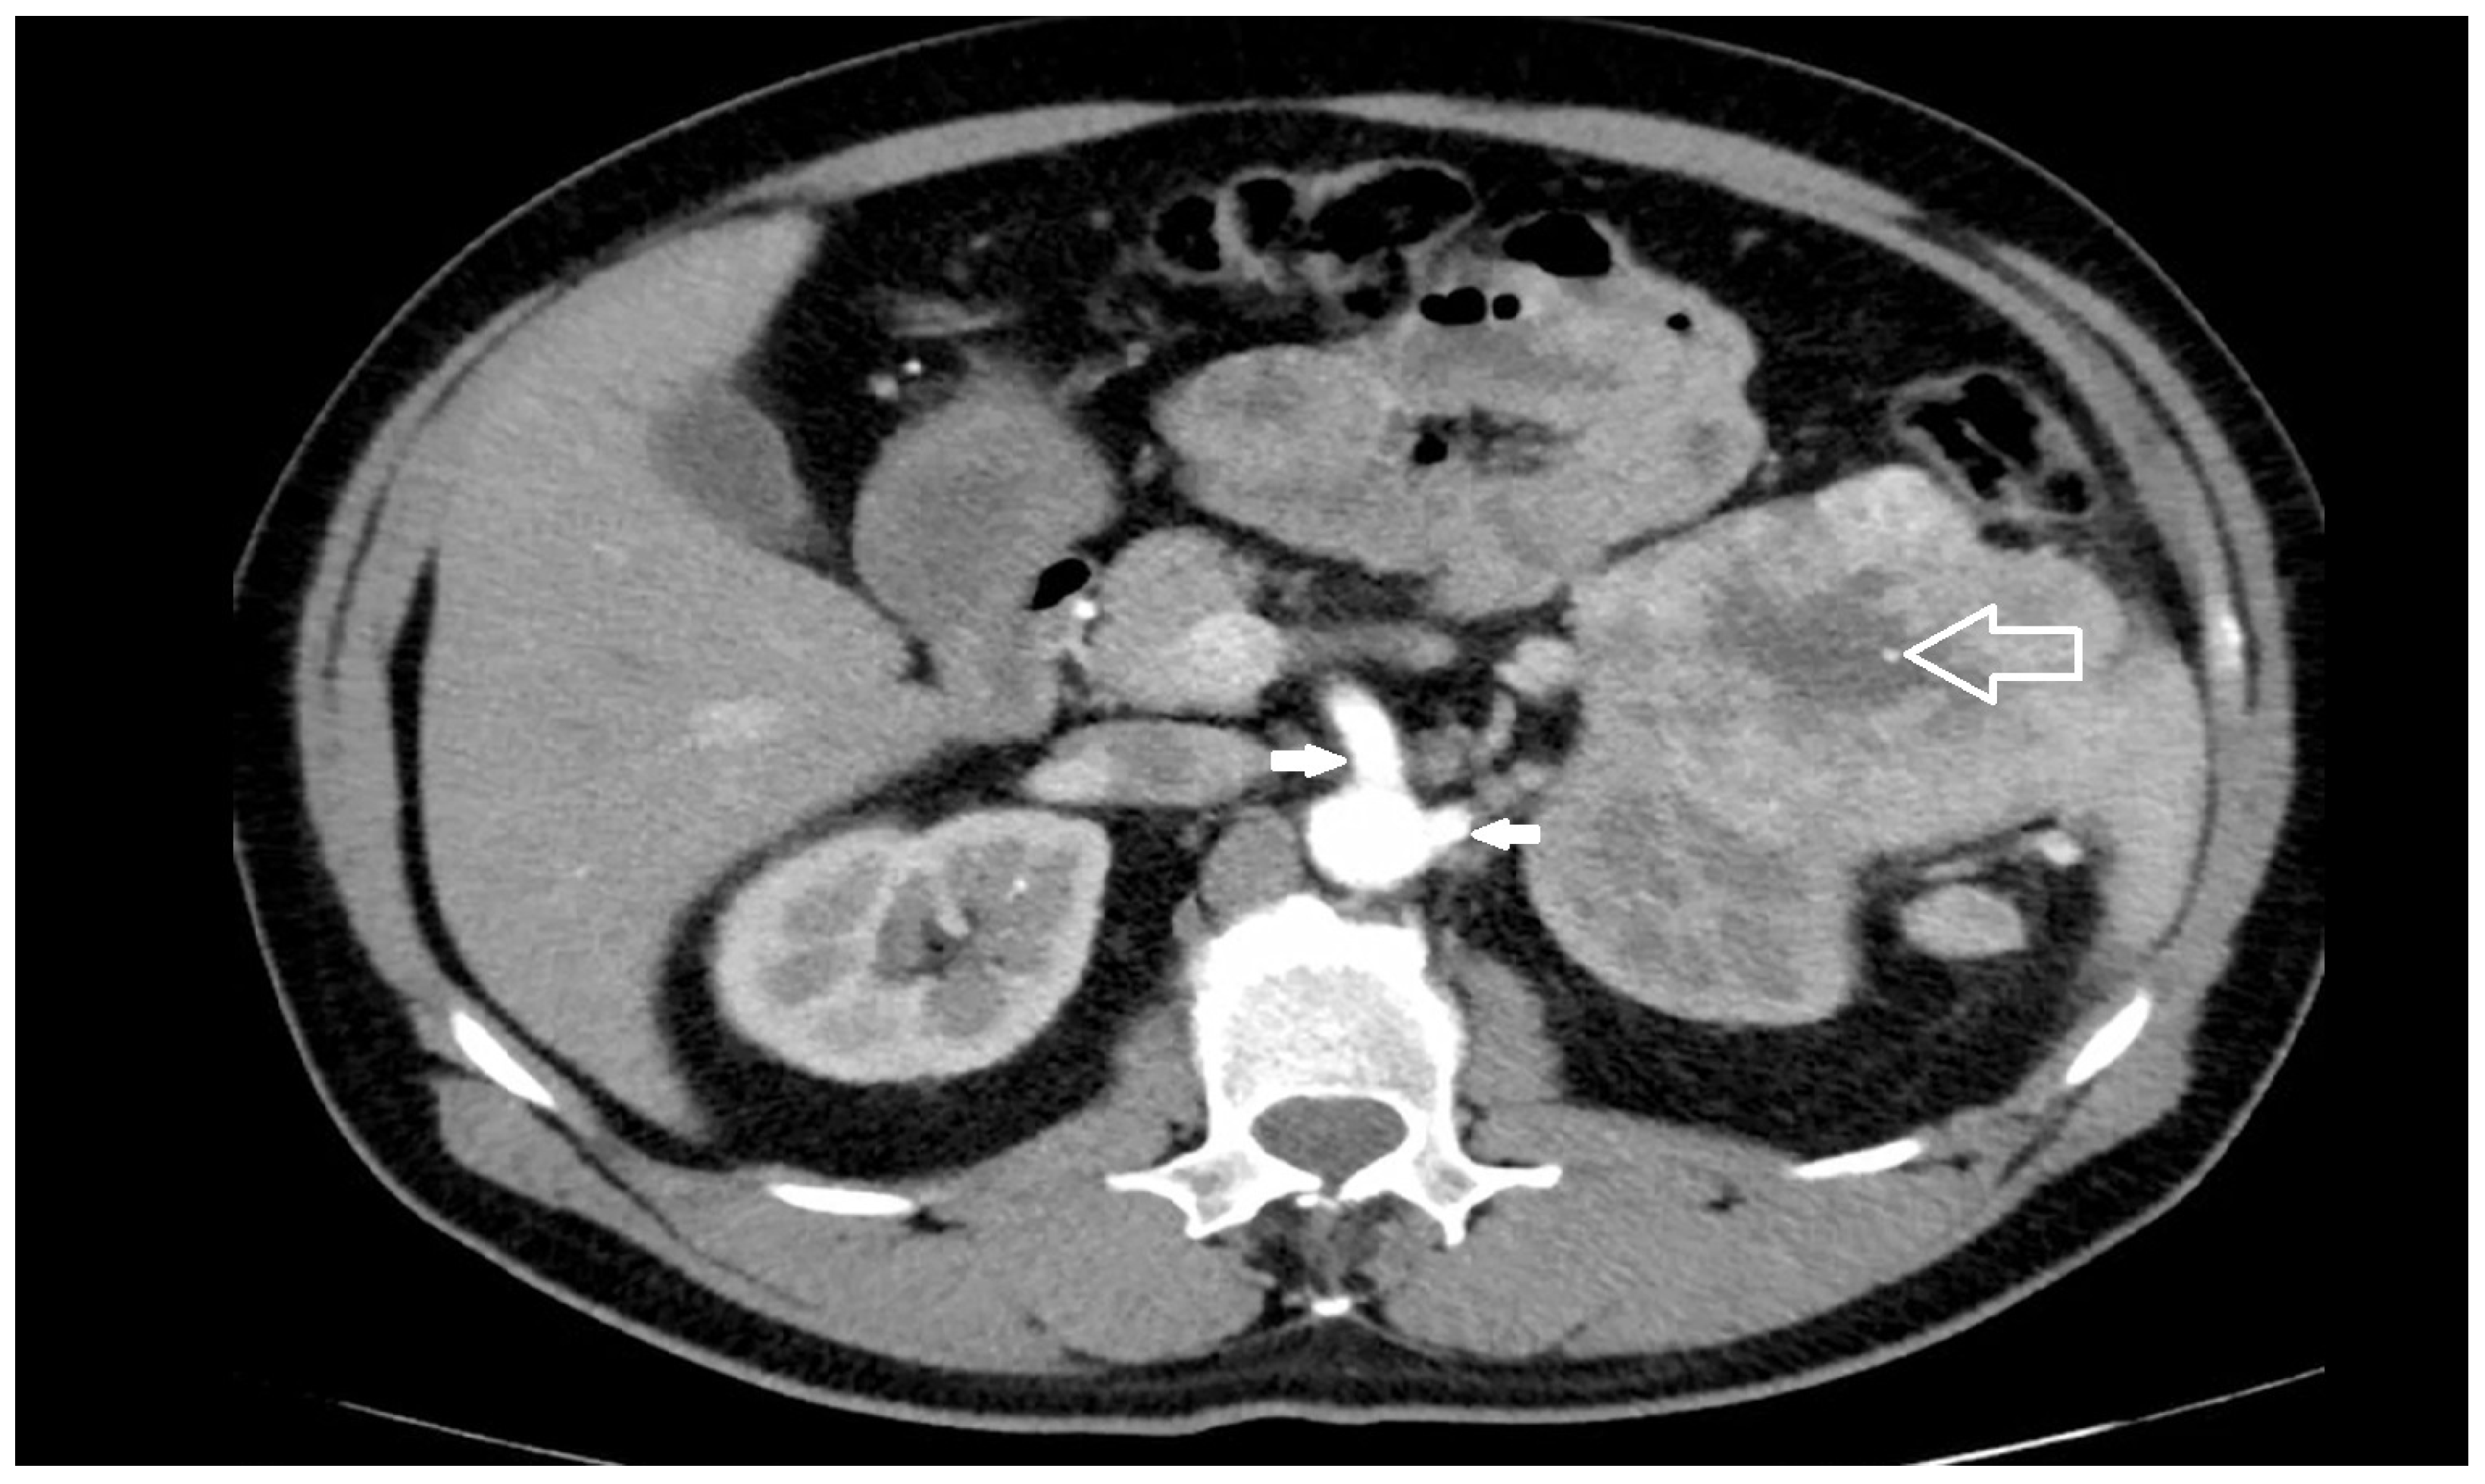

Risk factors most commonly reported for the occurrence of a iatrogenic injury of the SMA and/or CT during left nephrectomy/adrenalectomy are: the close spatial relations between renal and visceral arteries [5,6,7,8,9,10,11]; surgery indicated for large neoplasms of the left upper renal pole or left adrenal gland (Figure 2), or with extra-renal spread or bulky hilar lymph node involvement [15,21]; surgery indicated for inflammatory renal diseases or completion nephrectomy after partial resection with perivisceral inflammatory adhesion to the aorta and its visceral branches [15]; morbid obesity [35]; lack of surgeon’s experience [28,36].

Figure 2. Large renal cell cancer of the left upper kidney (empty arrow): close proximity of the origin of SMA and LRA (solid arrows) from the aorta is evident.